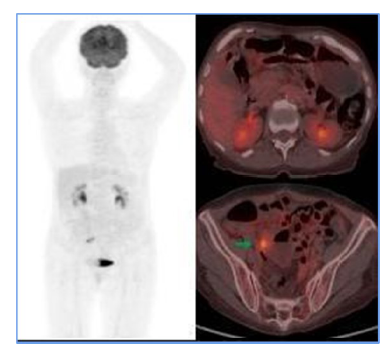

• July 22, 2021, PET-CT (F18-FDG): Supra- and infra-diaphragmatic hypermetabolic lymphadenopathies, suggesting glycolytic tumor activity; consideration of lymphoproliferative disease, diffuse thickening of the right ascending colon wall, and diffuse FDG uptake in the axial skeleton (Figure 1).

With these findings and the relevant clinical analysis, the diagnosis of IDCS was considered at the time, and treatment was initiated. The patient underwent 6 sessions of R-CHOP chemotherapy. Flow cytometry in the bone marrow showed aberrant plasma cells at 0.11%, and a PET-CT (F18-FDG), when compared to the initial study, reported resolution of supra- and infra-diaphragmatic adenopathy (See Figure 1). The scan also showed an iliac internal chain adenopathy with FDG uptake, surpassing liver uptake, which, based on Deauville criteria, scored a 4, thus indicating a partial response to treatment.

Figure 1

Initial PET CT. Hypermetabolic supra (yellow arrow) and infra diaphragmatic (blue arrow) adenopathy suggest tumor glycolytic activity. Diffuse mural thickening of the hypermetabolic ascending colon (green arrow) in the clinical context of suspected lymphoproliferative disease suggests extranodal involvement.

For staging, PET-CT (F18-FDG) is a crucial tool. Initially, it allowed for documentation of both nodal and extranodal involvement, establishing tumor viability and aiding in follow-up and evaluation of treatment response. The Deauville 5-point visual scale [7] was used to assess treatment response. In this case, the PET-CT documented persistent disease (Deauville 4), which influenced treatment decisions and led to escalation of the medical management. A subsequent PET-CT (F18-FDG) performed after rescue therapy demonstrated a complete metabolic response at the end of treatment [8].

In the case presented here, the patient showed a favorable response to chemotherapy, achieving complete remission and surviving for two years to date. Lymph node and extranodal involvement, along with immunohistochemical findings, enabled the diagnosis and timely treatment initiation (Figure 1). The partial metabolic response observed in the post-treatment PET (Figure 2) led to the decision to escalate the treatment to second-line RICE chemotherapy. Eventually, a new PET-CT (F18-FDG) post-treatment (Figure 3) confirmed a complete metabolic response.